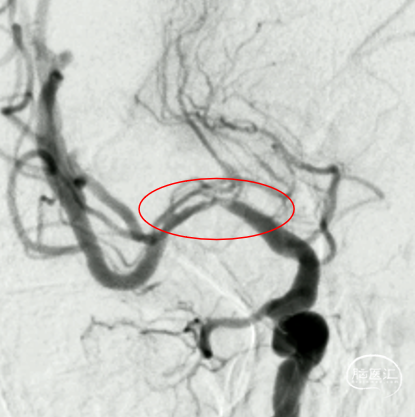

球扩后造影:狭窄明显改善,前向血流明显好转,未见血栓征象,球囊部分回收支架,撤出。

观察15min,未见弹性回缩,正侧位造影。